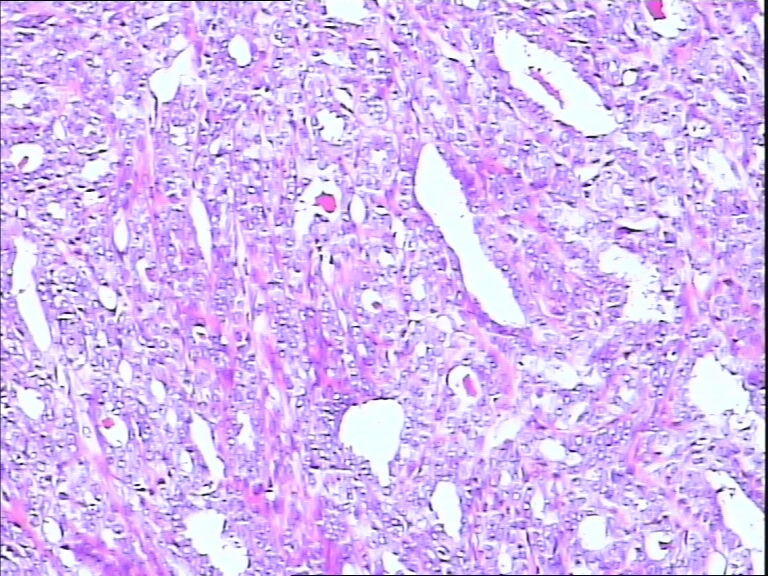

42y

左乳头有3mm结节

灰白不整形组织一块:0.7*0.5*0.4

导管内乳头状肿瘤